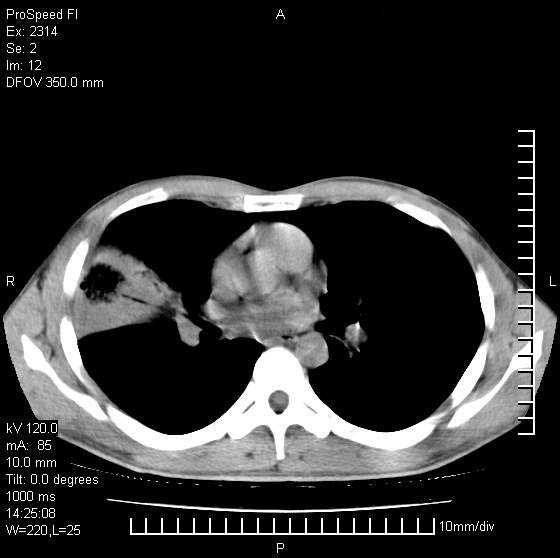

男性,再生障碍性贫血,入院前发热10天,最高40c,右侧胸痛,外院ct示右上,中肺边缘模糊的球性影(就是我现在图中标示的范围),考虑炎症,在我院使用头孢呋辛,洛美沙星10天,高烧消退,自感下午稍有发热,但今天ct示右上,中肺病灶明显扩大,还是考虑炎症,看其中的球型影是否霉菌感染??,是否能排除结核?

右肺中叶外侧段病变,上缘界限不清,下缘锐利,以段性发病为主,内见巨大空洞及空洞内容物,结合病史首先考虑:化脓性肺炎。不除外霉菌感染!

考虑霉菌感染.理由1\\有临床基础疾病,2\\有坏死的空腔,其内可见软组织影.

片状高密度影内见空洞影,内可见球形软组织密度影,并有新月征,考虑霉菌感染.